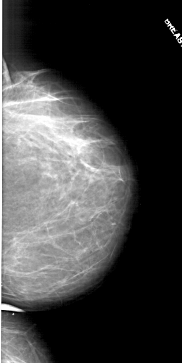

A_1711_1.LEFT_MLO

LEFT_MLO LINES 6736 PIXELS_PER_LINE 2956 BITS_PER_PIXEL 12 RESOLUTION 43.5 OVERLAY